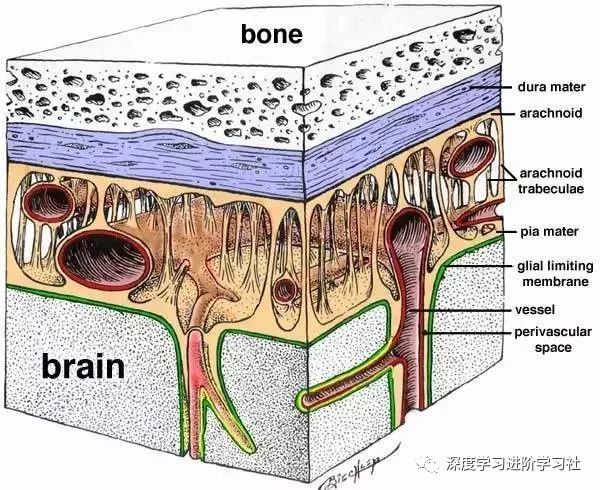

你的头骨下面,又是一大堆东西,之后才是你的大脑:

在你的头骨下面,大脑周围有三个膜,将大脑环绕:

在外面,有硬脑膜,坚固耐用,防水。硬脑膜与颅骨齐平。我听到有人说,大脑中没有疼痛感觉区,但硬脑膜实际上能感觉疼痛,且和你的面部肌肤一样敏感,硬膜上的压力或挫伤往往造成了人们严重的头痛。

然后下面是蛛网膜,这是一层皮肤,然后是带有弹性的纤维的开放空间。我一直以为我的大脑只是漫无目的地漂在我大脑中的某种液体里,但实际上,脑外和颅骨内壁之间的唯一真正的空间差距是这个蛛网膜。这些纤维稳定了大脑的位置,因此不能动作太大,他们充当减震器,当你的头撞到东西。这个区域充满了脊髓液。

最后,是软脑膜,和脑外融合的很精巧的皮肤层。你知道,当你看到一个大脑,它总是覆盖着恶心的血管。但这些并不是真正在大脑的表面上,它们埋设在里面。

从左到右是皮肤(粉红色),然后是两个头皮层,然后是头骨,然后是硬脑膜,蛛网膜,最右边是只由软脑膜覆盖的大脑。